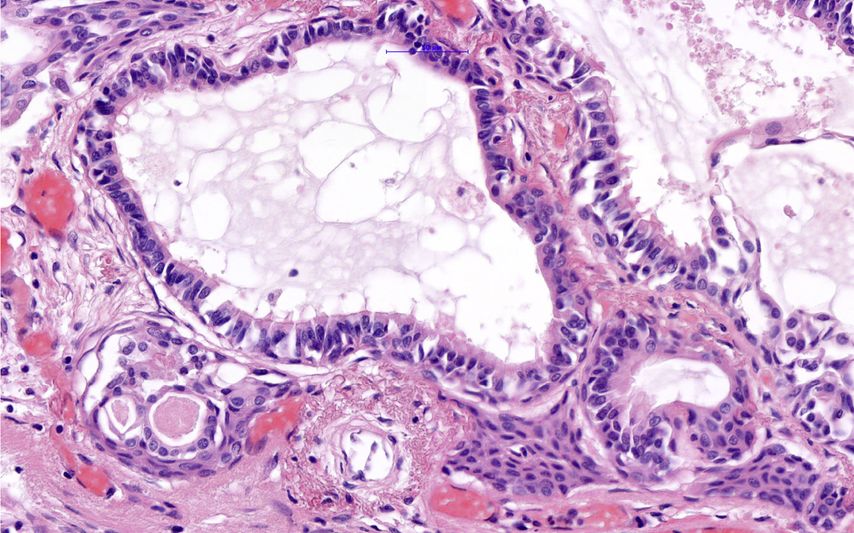

Histologisch zeigt der Tumor einen Mix aus verschiedenen Zellen: Es finden sich hochzylindrische Zellen mit Zilienbesatz (wie die normalen Zylinderepithelien), plattenepithelial differenzierte Zellen (wie eine Metaplasie mit/ohne Atypien), schleimproduzierende Becherzellen sowie Basalzellen. Die Tumorzellen exprimieren Keratin 5 (vorwiegend Basalzellen) und 7 (alle übrigen Zellen), sind teilweise positiv für den thyroidalen Transkriptionsfaktor 1 (TTF1), aber negativ für CDX2 – zeigen also keine intestinale Differenzierung. Auch eine Untersuchung auf den „hepatocyte nuclear factor 4 alpha“ (HNF4A) war negativ. Für die Becherzellen wurde eine positive Reaktion auf Mucin 5AC (MUC5AC) und MUC6 berichtet. Der Proliferationsindex Ki-67 war mit <5% sehr niedrig.

Abb. 4:Mischung verschiedener Zellen als Charakteristikum dieses Tumors: Zilienzellen, Becherzellen, Basalzellen, Plattenepithelzellen. Maßstab 50µm

Der ziliäre papilläre mukonoduläre Tumor der Lunge ist eine neue Entität, der eine charakteristische Morphologie aufweist (Abb. 1–4). Aufgrund der bisherigen Berichte kann von einer geringen Malignität ausgegangen werden. Die molekularen Signaturen lassen aber die Möglichkeit einer Rezidivierung und eventuell sogar einer Metastasierung offen.Dementsprechend kann eine Prognose nicht mit Sicherheit abgegeben werden. Eine engmaschige Kontrolle in den ersten fünf Jahre nach Diagnose ist zu empfehlen.